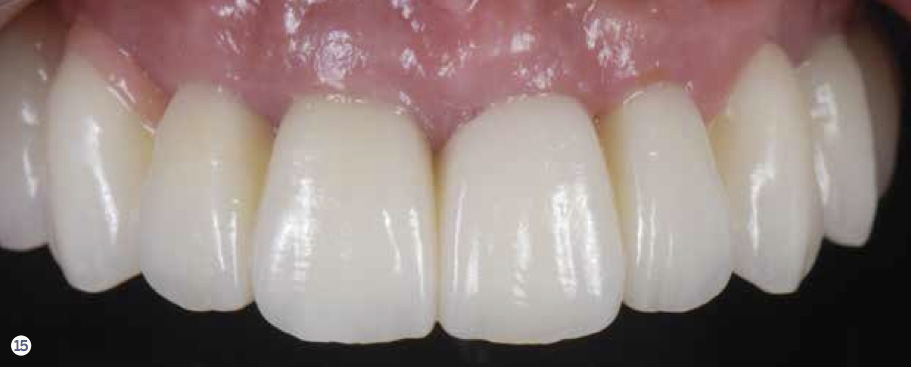

Fig 15. Pretreatment and posttreatment views of the implant-supported reconstruction. Notice the favorable changes in the gingival outline and tooth proportions.

Figure 15